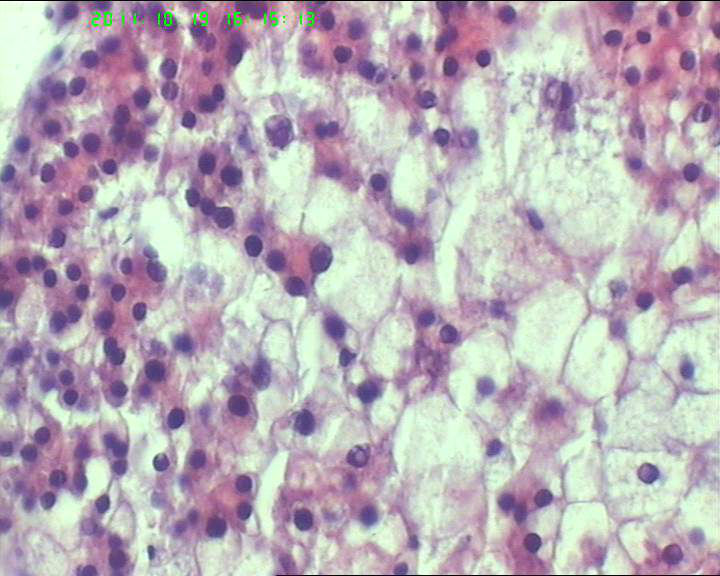

71岁男性肝脏占位,ct示低密灶,大三阳,afp高,转氨酶略高。该诊断什么呢?

• 71岁男性肝脏占位,ct示低密灶,大三阳,afp高,转氨酶略高。该诊断什么呢?图1